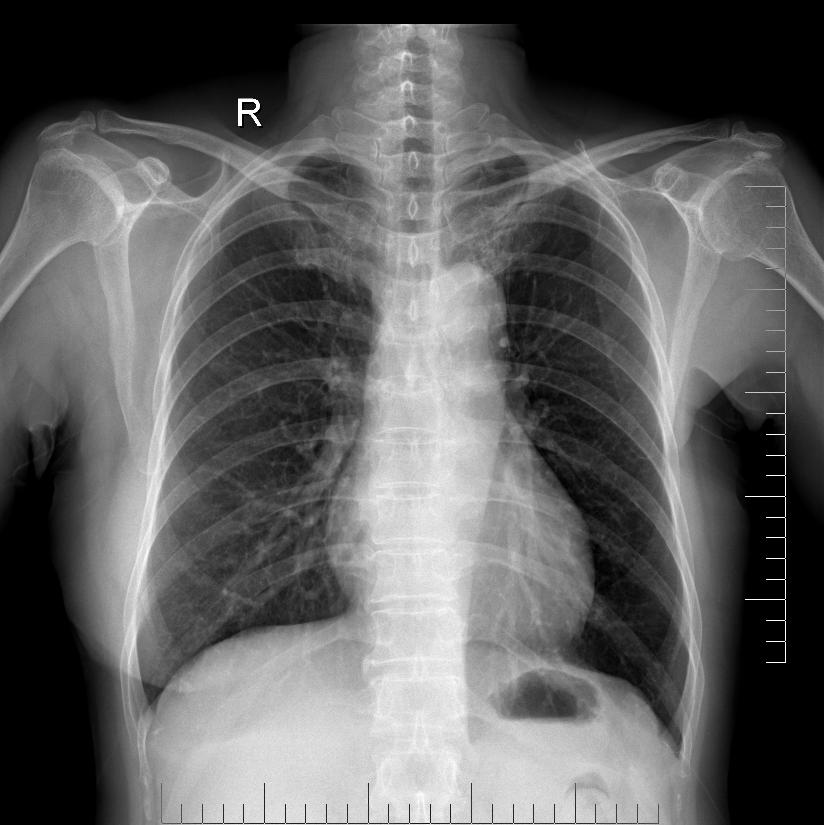

标题: X4211:F64Y,胸骨局部小骨质突起

患者:女,64,头晕10年,再发3天,入院体查时发现

考虑良性骨瘤、骨软骨瘤之类的

考虑骨瘤,另似乎左侧乳房缺如

胸骨骨软骨瘤可能。骨瘤在颅骨以外区域生长者,良性的很少。

支持考虑骨瘤,另左侧乳房缺如!

左侧乳房缺如----------------------详细问问病史!!!

是前肋软骨钙化。